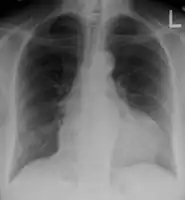

-

Ultrasounds showing a pericardial effusion in someone with pericarditis

A pericardial effusion as seen on CXR in someone with pericarditis

The diagnosis of tamponade can be confirmed with trans-thoracic echocardiography (TTE), which should show a large pericardial effusion and diastolic collapse of the right ventricle and right atrium. Chest X-ray usually shows an enlarged cardiac silhouette ("water bottle" appearance) and clear lungs. Pulmonary congestion is typically not seen because equalization of diastolic pressures constrains the pulmonary capillary wedge pressure to the intra-pericardial pressure (and all other diastolic pressures).